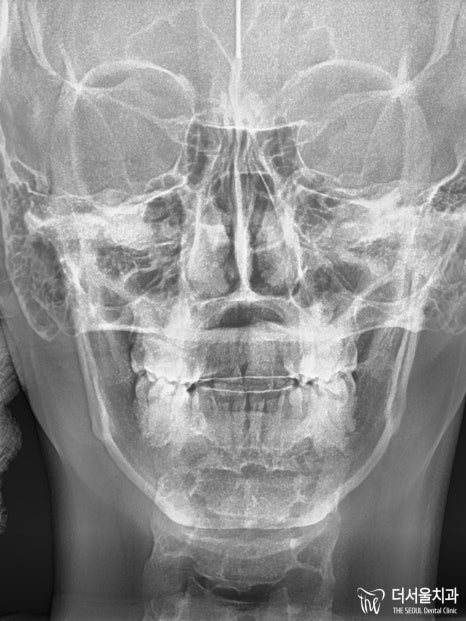

【 초진 】

이분께서는 미국 국적을 갖고 있는 외국인 환자로

마무리가 2급 부정교합으로 되어있더라고요^^..

2급 부정교합 그리고 # 26 크로스 바이트까지

여러 아쉬움이 남는 것으로 확인되었는데요.

환자분의 얘기를 들어보니

편하게 다물어지지 않고 삐뚠 느낌이 든다며

빠른 시일 내에 개선을 원하고 계셨습니다.